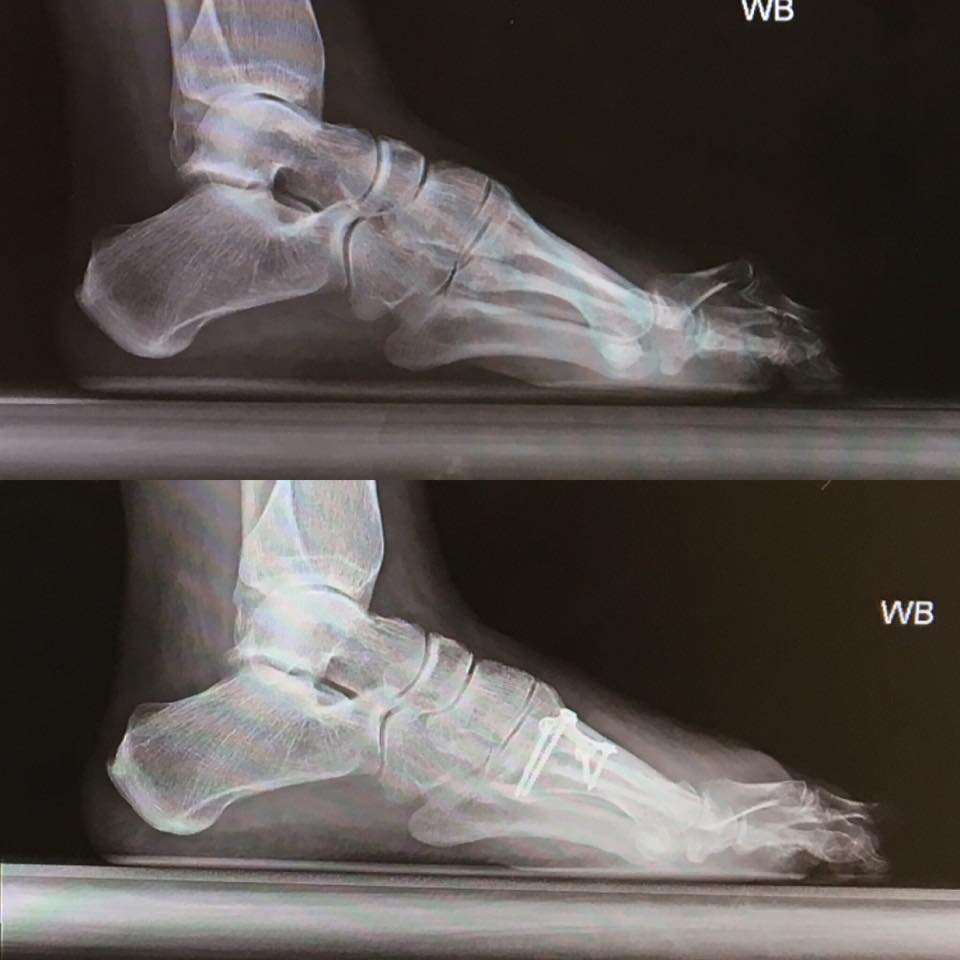

I came to HSS for a consultation after the recommendation of my Physical Therapist at the time. I was in constant pain in my foot and my foot was stuck in "dorsiflexion" from previous surgeries. Quite simply I always looked like an elf and my toes pointed upwards. When I met with Stephen Costigliola and Dr. Scott Ellis I felt confident in the plan they presented to correct the issue. Throughout the time period from consultation to surgery, Stephen and Dr. Ellis remained available if a question or concern presented itself. After I completed a Half Marathon in November the pain increased and was not relieved by any methods. I reached out for help and the amazing staff at Dr. Ellis' office (Carlos) advised me that my surgery could be moved up by 2 months.

On January 10, 2017 I went to HSS and had the following performed:

Toe Fusions, Osteotomy Metatarsal, Release of Metatarsophalenageal Joint in my Foot, Recession of Gastrocnemius and Lengthening of Tendon.